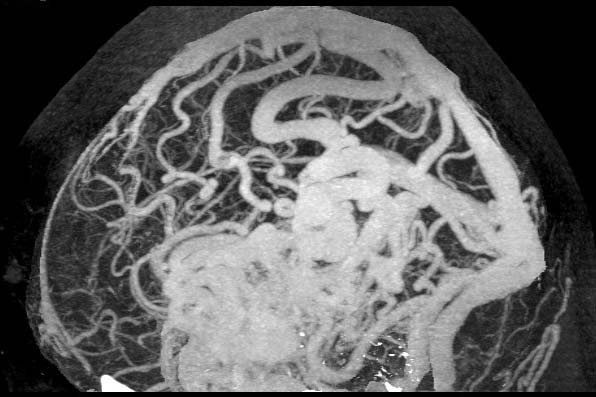

Arteriovenous malformation

0.5mmx4, Pitch 3.5, 200mAs

MIP